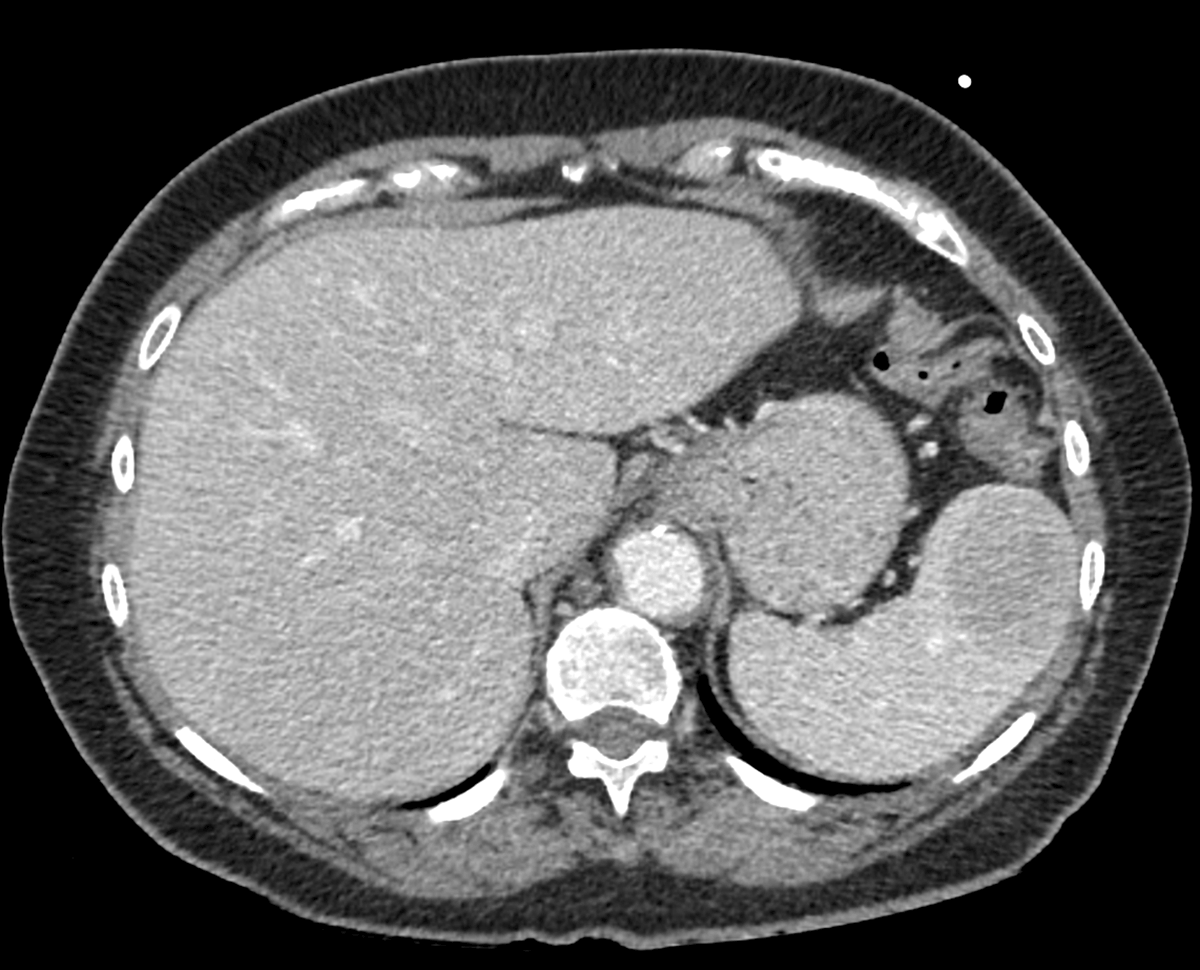

Figure 1

Axial Computed Tomography in the porto-venous phase depicts a sharply delineated lesion anteriorly in the spleen with relative hypo-enhancement compared to the surrounding splenic parenchyma.